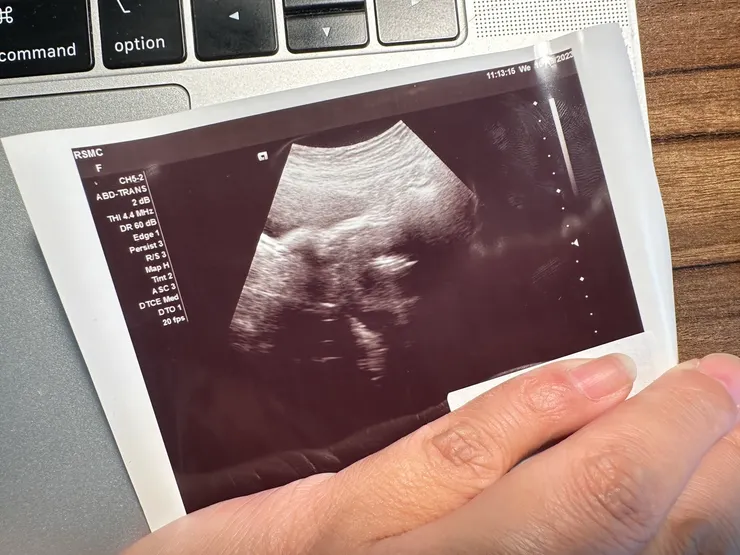

抵達診所後,是由護士來接我們進去診間中,植入前她和她說明了植入後的注意事項(包含植入後需臥床休息兩天、不要提超過五磅的重物、還有植入後的用藥調整)後,便請她換上手術服(包含手術服、頭套、鞋套),另外給了一顆神奇的藥物,說吃完之後就不會覺得緊張了(所以接下來在等待植入的過程中,只有我一個人焦慮地坐在椅子上面在診間裡滑來滑去),在植入前先幫她做了腹部超音波(這邊大家要記得脹尿唷!我們在吃早餐時我就跟她說要脹尿,結果她想說應該還好吧!所以就去尿了,結果到了診所後還是多喝了一小瓶水),做完基本檢查之後,就讓我們靜靜的等待醫生的到來,確認最後要植入的胚胎。

聽女友分享在手術室內的一切(雖然她說其實躺著沒有多久她就睡著了,而且在15分鐘過去後護士進來確認她的狀況時,她還以為自己已經回到飯店,正在心理質疑著這人怎麼可以自己進來房間XDD),RSMC的大家都很貼心也很溫柔,推著她出去的護士也跟她說這一切很順利,胚胎植入的位置很漂亮、照超音波時膀胱也很清楚的看到,這一切都是順利的結束了